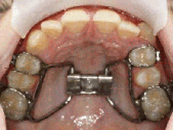

Beeinflussung der Unterkieferlage durch Federn, die an der festsitzenden Apparatur im Mund befestigt werden. Wir verwenden dazu beispielsweise einen BioBiteCorrektor oder vergleichbare Apparaturen.